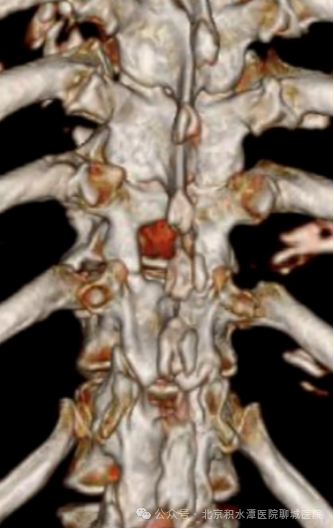

术前影像:T11/12胸椎黄韧带骨化,胸椎椎管狭窄

患者入院后,通过影像学分析,患者黄韧带骨化范围以T11/12为著,病变位置位于T11/12间隙,认为UBE技术更适用解决患者病痛。

术后影像:去除少量骨质扩大胸椎椎管

并取出骨化的黄韧带